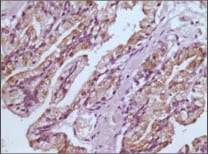

Immunohistochemical analysis of paraffin-embedded human prostate tissues using GSTP1 mouse mAb with DAB staining.